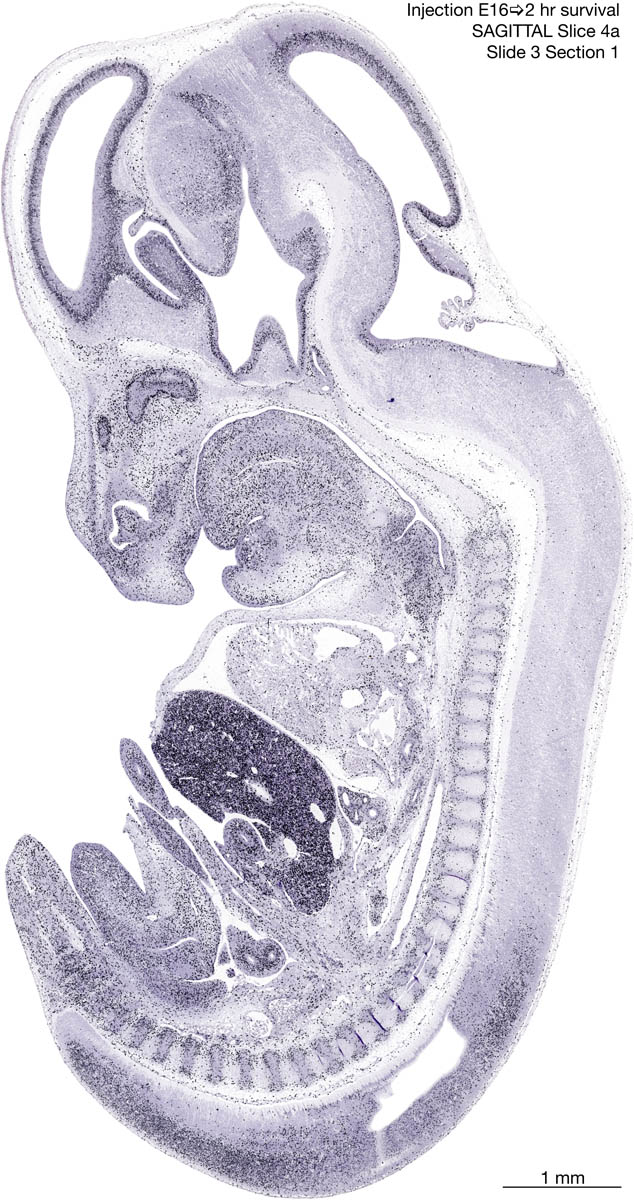

E16 2hr Survival Archived Images-Sagittal The following images are from a paraffin-embedded sagittally-sectioned E16 rat embryo exposed to tritiated thymidine 2 hours before death. Download: Large | High Res Download: Large | High Res Download: Large | High Res Download: Large | High Res Download: Large | High Res Download: Large | High Res Download: Large | High Res Download: Large | High Res Download: Large | High Res Download: Large | High Res Download: Large | High Res Download: Large | High Res Download: Large | High Res Download: Large | High Res Download: Large | High Res Download: Large | High Res Download: Large | High Res Download: Large | High Res Download: Large | High Res Download: Large | High Res Download: Large | High Res Download: Large | High Res Download: Large | High Res Download: Large | High Res Download: Large | High Res Download: Large | High Res Download: Large | High Res Download: Large | High Res Download: Large | High Res Download: Large | High Res Download: Large | High Res Download: Large | High Res Download: Large | High Res